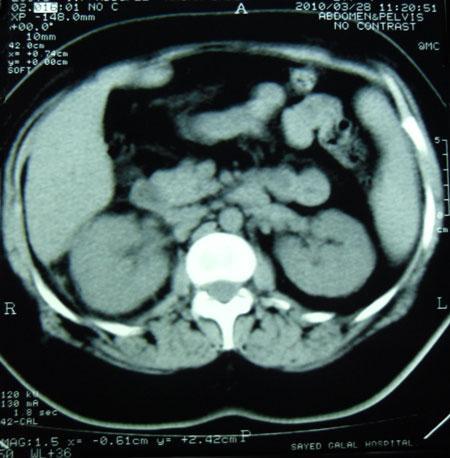

Chronological Photo-sequence

of the case progression

-On presentation: